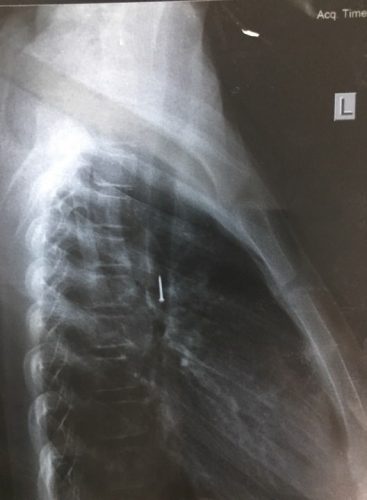

| Hình ảnh phim chụp X - quang thẳng/nghiêng xác định có đinh ghim nằm sâu trong phế quản. Ảnh: V.H. |

Sau tai nạn, bé ho sặc sụa, khạc ra máu, nôn nhiều nên được người nhà đưa đến Bệnh viện Đa khoa Mộc Châu (Sơn La) khám. Tại đây, qua chụp X-quang các bác sĩ xác định lồng ngực cháu bé có dị vật hình đinh ghim. Bé Thương được chuyển tới Bệnh viện Nhi Trung ương để theo dõi và tiếp tục điều trị.

Tại Bệnh viện Nhi Trung ương, các bác sĩ tiến hành chụp X-quang cho thấy có dị vật là một chiếc đinh ghim dài khoảng 1,5 cm nằm ở vị trí thành ngực của bé gái. Các bác sĩ đã hội chẩn và quyết định phẫu thuật nội soi lấy dị vật ra khỏi lồng ngực của bé.